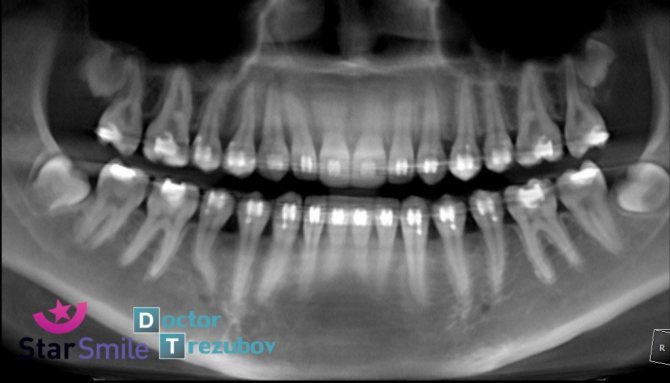

- телерентгенограмму;

- ортопантографию;

Снимок телерентгенограммы позволяет выявить важные параметры перед началом ортодонтического лечения: угол наклона зубов, соотношение мягких и костных тканей, степень смещения элементов и их расположение относительно друг друга